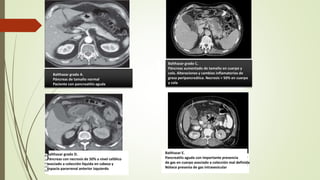

Balthazar grado A.

Páncreas de tamaño normal

Paciente con pancreatitis aguda

Balthazar grado C.

Páncreas aumentado de tamaño en cuerpo y

cola. Alteraciones y cambios inflamatorios de

grasa peripancreática. Necrosis > 50% en cuerpo

y cola

Balthazar grado D.

Páncreas con necrosis de 50% a nivel cefálico

asociado a colección líquida en cabeza y

espacio pararrenal anterior izquierdo

Balthazar E.

Pancreatits aguda con importante presencia

de gas en cuerpo asociado a colección mal definida

Nótece presenia de gas intravesicular